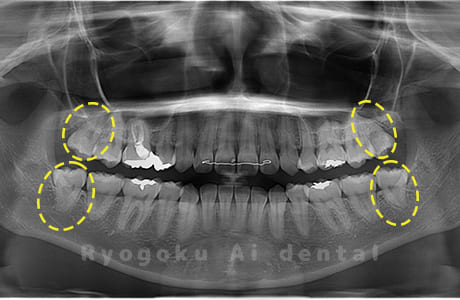

Case03

-

- 原因

- 上顎、下顎の親知らず

- 治療内容

- 上下4本の親知らずを抜歯したケースです。

<リスク・副作用>

手術後は痛み、腫れ、痺れなどの副作用が生じる場合があります。